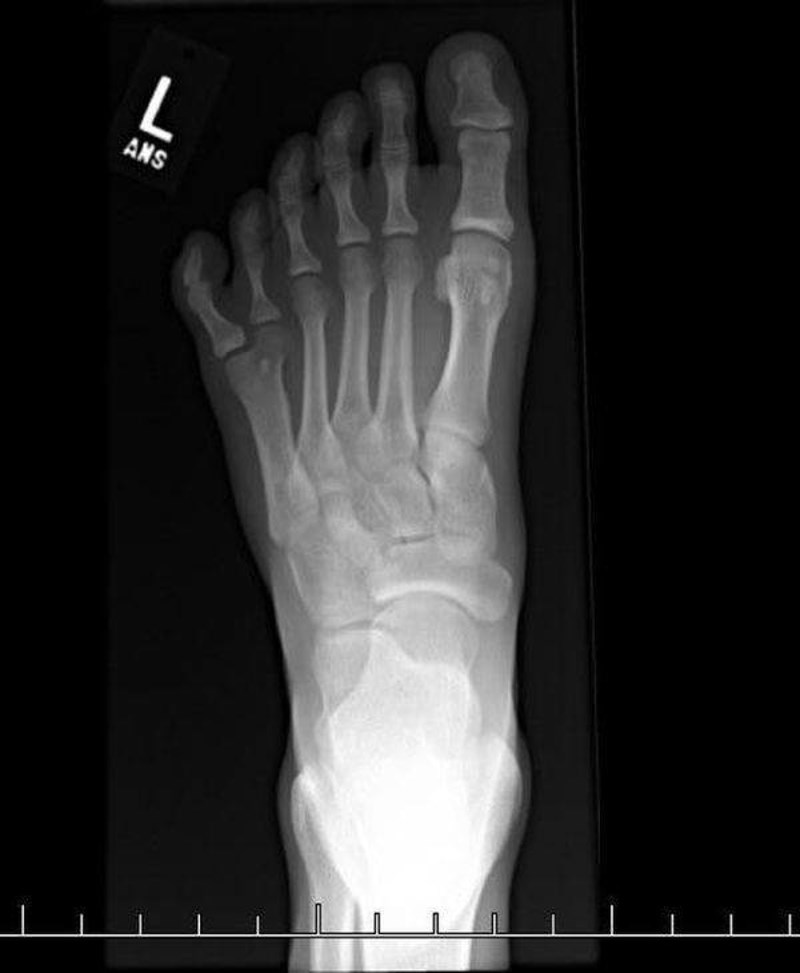

13. Rendgenska snimka stopala s 6 prstiju